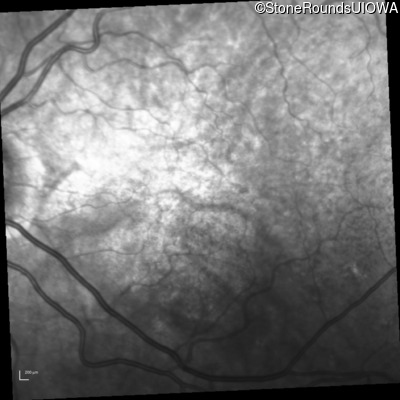

Infrared Fundus Photograph - Left - 20/30 -2 sc

Exemplar